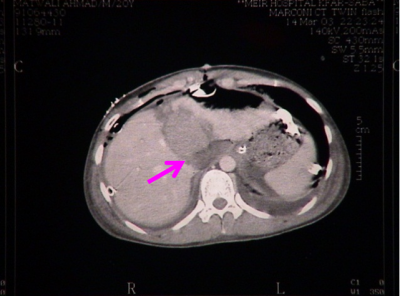

- טומוגרפיה ממוחשבת - בדיקה זו יכולה להראות את היקף הנזק ומיקומו. בדיקה זו אפשר לבצע בחולים שהם יציבים המודינמית, והיא בדיקת הבחירה (תצלום 7.10 ). ניתן להדגים גם דימום פעיל מהכבד על ידי הדגמת דליפה של חומר ניגוד באזור החבלה (תצלום 8.10).

בנוסף ב- CT אפשר לראות גם פגיעות באיברים אחרים (תצלום 9.10) כולל כלי דם (תצלום 10.10).